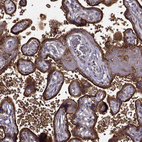

Immunohistochemistry analysis in human placenta and skeletal muscle tissues using HPA073622 antibody. Corresponding YIPF5 RNA-seq data are presented for the same tissues.